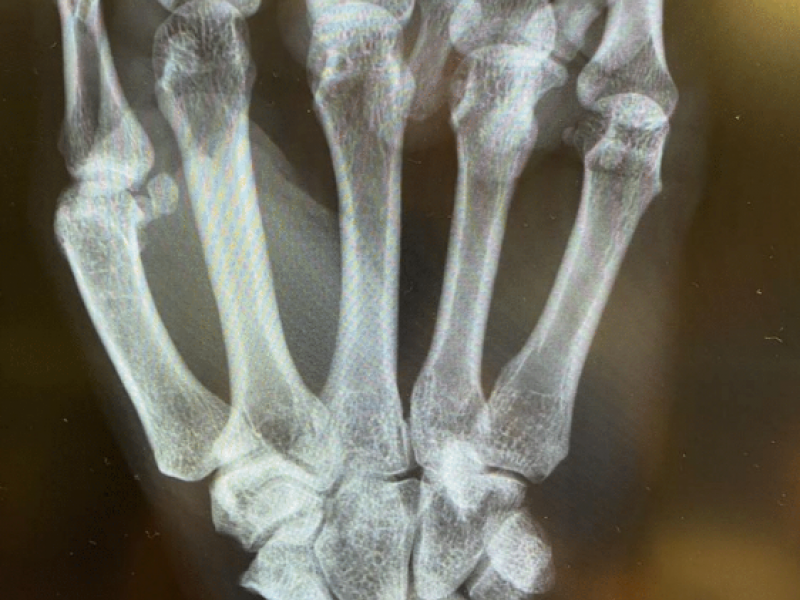

A 40 yo M presents to the ED with R wrist pain. Onset was